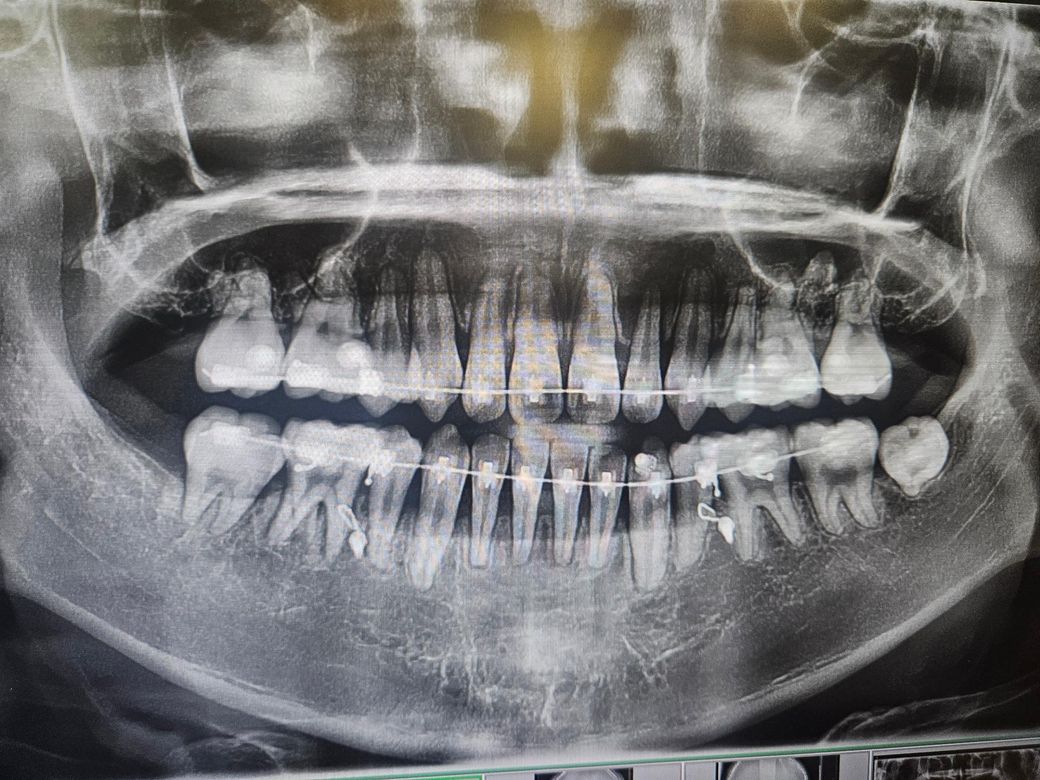

첫번째가 교정 시작할 때, 두번째가 현재입니다.

약 2년정도 되었고 육안으로 보기에도 잇몸이 많이 내려간 것 같은데 의견이 궁금합니다.

• 2번 째 사진

잇몸뼈가 꽤 내려간 것으로 보입니다. 교정 후에도 잇몸관리를 잘해주셔야 할 것 같습니다.

사진으로 갔을 경우에는 치조골의 양이 어느 정도 내려간 것으로 보입니다. 치즈볼의 양이 내려갔을 경우 치아를 잡고 있는 치조골의 양이 줄어들었기 때문에 잇몸에 염증이 생기지 않도록 주의해서 관리를 하는 것이 좋습니다.

엑스레이 사진으로는 잇몸이 아니고 잇몸뼈 상태를 관찰합니다. 교정 후로 잇몸뼈가 다소 낮아지고, 치아 뿌리도 짧아진 것이 관찰은 되지만 엄청 심각한 편은 아닙니다. 앞으로 관리 잘해주시면 됩니다. 교정 후 잇몸, 잇몸뼈 수축 그리고 치근 흡수 부작용은 얼마든지 있을 수 있습니다.